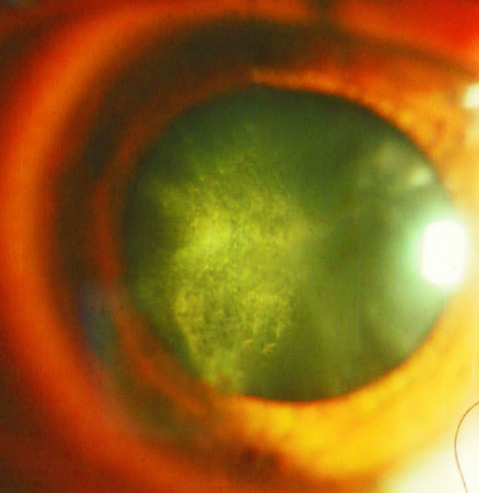

Nos ensaios clínicos, pessoas que tiveram catarata senil por menos de 7 anos tiveram os resultados mais rápidos e melhores. Pessoas com catarata de 7 a 15 anos ainda tiveram bons resultados, mas pessoas que mantiveram catarata por mais de 15 anos tiveram os resultados menos benéficos, embora mesmo assim ainda tenham conseguido obter melhorias.

Foi demonstrado que os colírios Can-C têm efeitos mensuráveis em apenas 1 mês de uso! No entanto, é recomendado que, para eficácia máxima, a administração seja continuada por um período não inferior a 3-5 meses. Como a maioria dos ensaios clínicos foi medida em períodos de 3 e 6 meses, um período de 6 meses deve ser considerado.